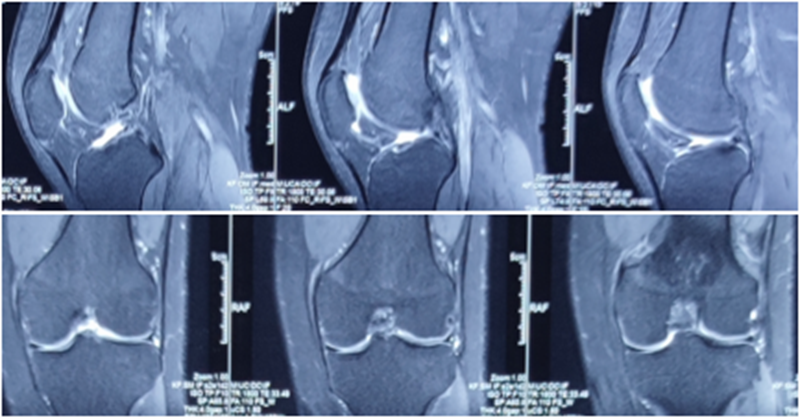

典型病例,张X,男,18岁,因扭伤致左膝关节疼痛伴活动受限1月余入院。

诊断:1.左膝前交叉韧带损伤;2.左膝外侧半月板损伤合并囊肿。

手术方案:左膝关节镜下清理、滑膜切除、外侧半月板部分切除成形、前交叉韧带重建术。

术前MRI

术后MRI